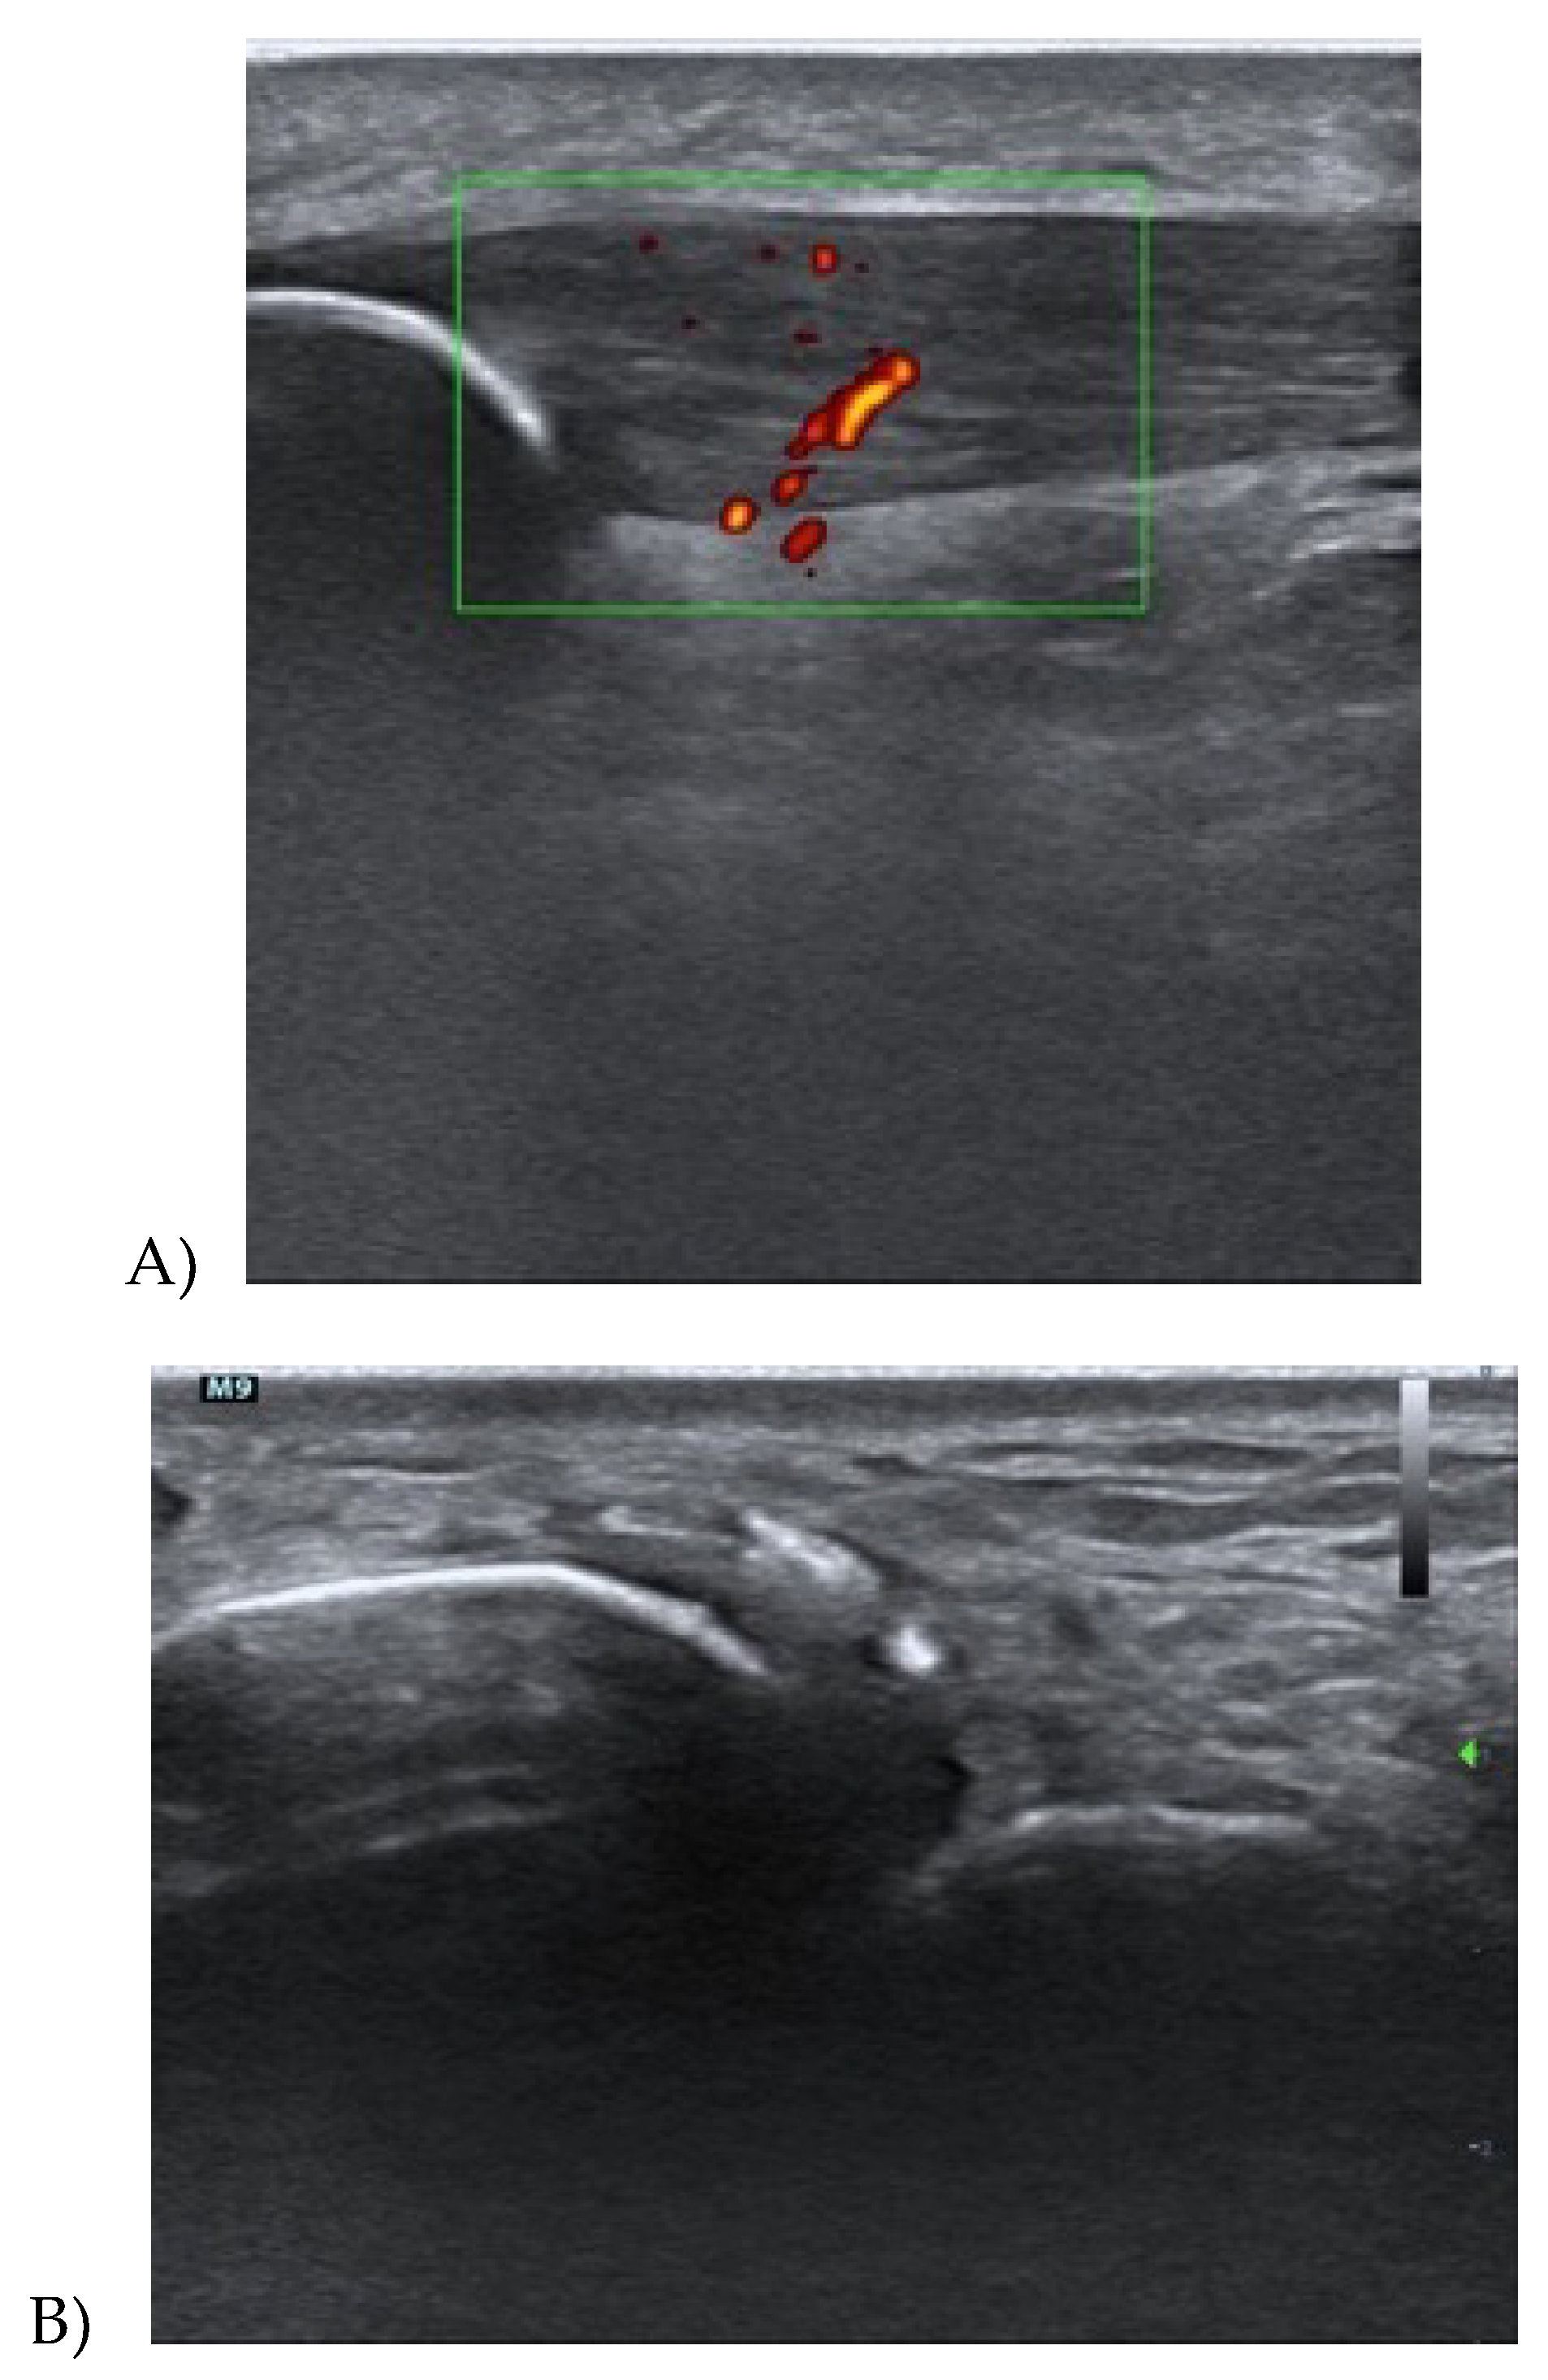

3.1. Achilles Tendinopathy

3.2. Patellar Tendinopathy

3.3. Quadriceps Tendinopathy

3.4. Proximal Hamstring Tendinopathy

3.5. Gluteus Tendinopathy

3.6. Treatments Using Ultrasound Imaging